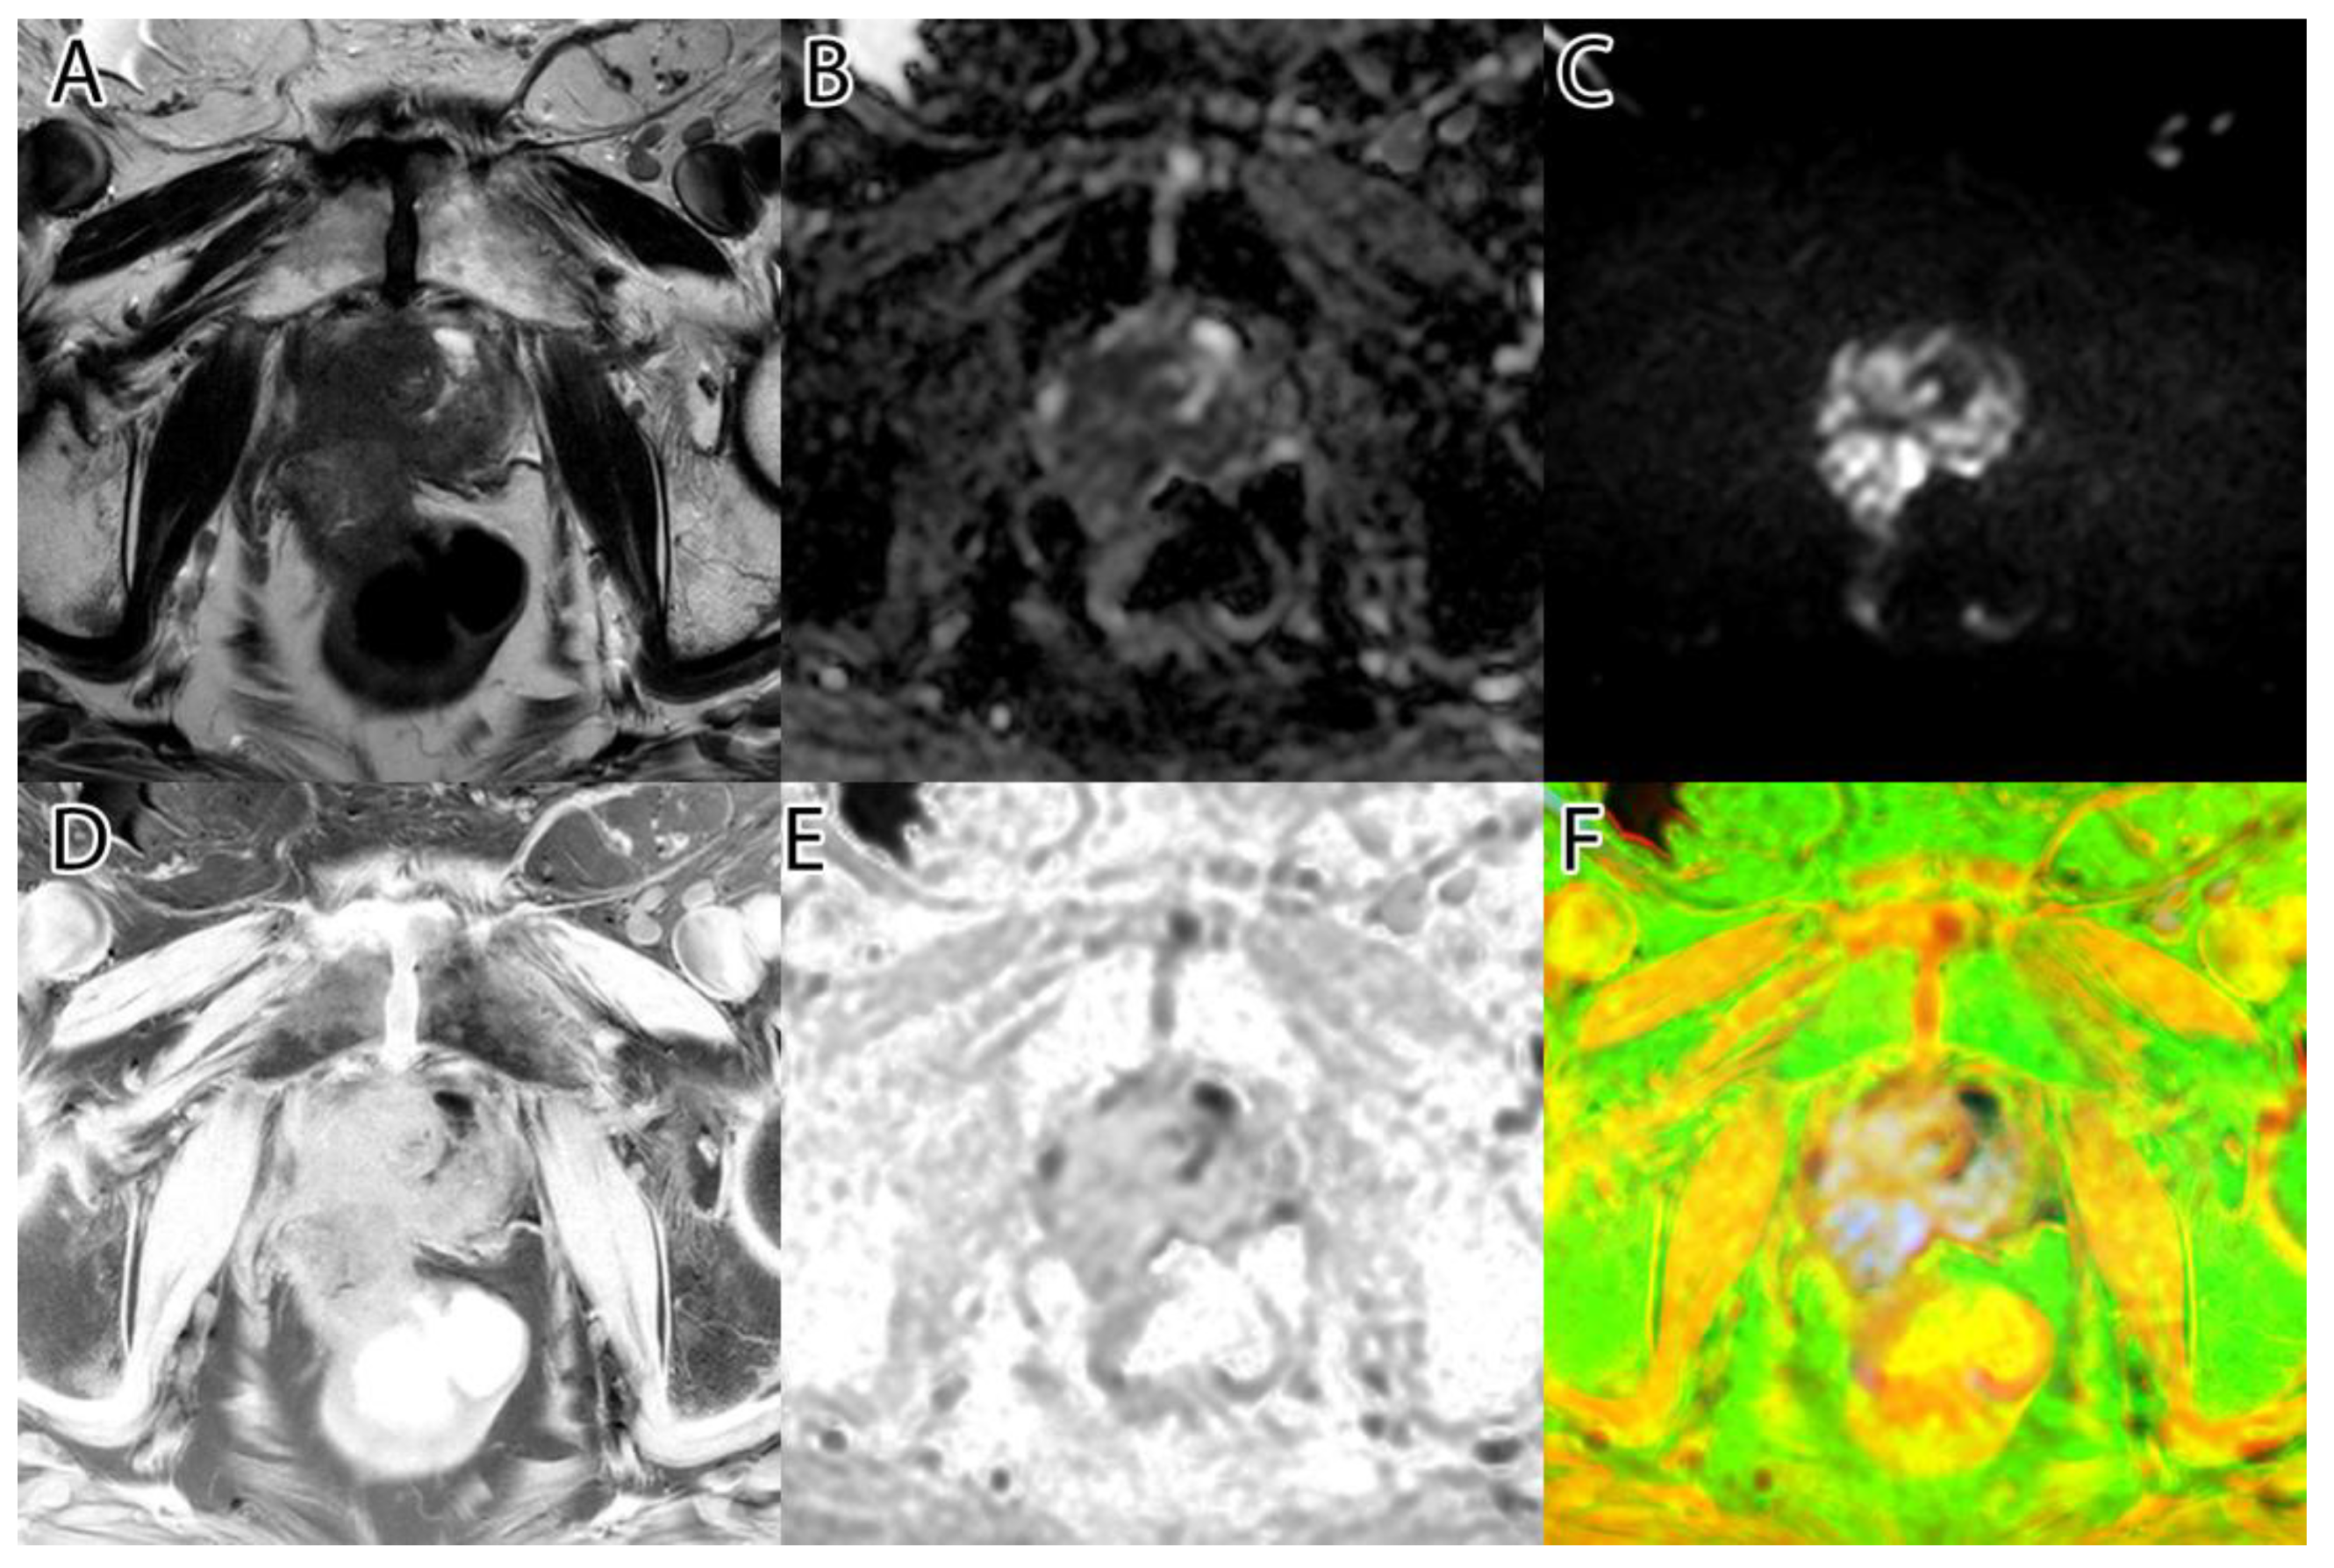

The sixth and final step was to compute the final intensity mask by subtracting the square root from the square sum of the alpha–beta channels and subtracting the resulting value from the luminance. The resulting intensity image can be seen in Figure 2B and Figure 3B. By adding the ‘jet’ color map to it, we obtained a colored intensity map that highlights the tumoral areas, as seen in Figure 2C and Figure 3C.

Figure 2. PI-RADS 2 patient: (A)—T2WI; (B)—ADC; (C)—DWI; (D)—RGB fused image; (E)—grayscale tumor intensity image; (F)—‘jet’-mapped tumor intensity image.

Samples of the computed tumor intensity images can be seen in Figure 2 for a PI-RADS 2 patient and in Figure 3 for a PI-RADS 5 patient. Notice the difference in “jet” intensity between the control patient and the patient with extraprostatic invasion.